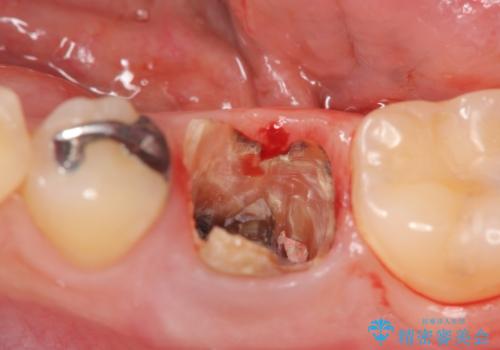

- 銀歯が揺れる、噛むと痛い、と治療を希望され来院されました。

銀歯・レジンコアを除去したところ、薄い残存歯質に亀裂が入り、保存が難しい状況が認められました。